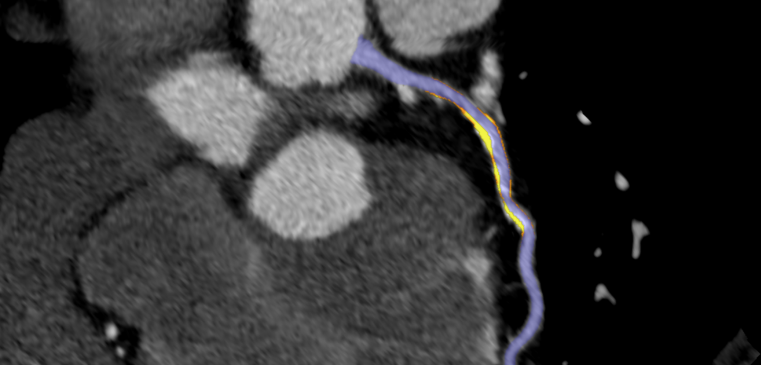

In terms of diagnosis, the review highlighted research that showed automatically generated, fully quantitative CMR MBF pixel maps to have high diagnostic performance for detecting significant CAD. A study of patients with known or suspected CAD revealed that a strong, independent predictor of adverse cardiovascular outcomes was provided by the automatic measurement of reduced MBF and myocardial perfusion reserve using artificial intelligence quantification of CMR perfusion mapping.